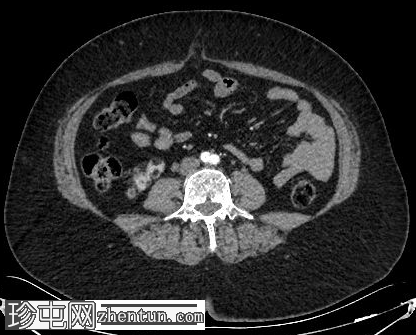

轴位增强扫描

动脉期

肝脏内可见多发边界清晰的脂肪结节状病变,最大病变位于肝脏VII段,直径15 mm

双肾可见多发脂肪肿块,右肾最大病变直径达45 mm,左肾最大病变直径20 mm

肾血管平滑肌脂肪瘤是结节性硬化症最常见的腹部表现,通常为多发性、双侧性,且体积大于散发性病变。血管平滑肌脂肪瘤。肝脏血管平滑肌脂肪瘤虽然不常见,但却是公认的肾外表现,其影像学特征与肾脏血管平滑肌脂肪瘤相似,包括CT扫描可见肉眼可见的脂肪,这使得诊断成为可能,且无需侵入性检查。

肾脏和肝脏中富含脂肪的血管平滑肌脂肪瘤可能仅有轻微或无明显的对比增强,仅表现为衰减值的轻微升高,反映血管和间质成分的增强。这些病灶内肉眼可见的脂肪具有高度特异性,有助于将血管平滑肌脂肪瘤与其他肾脏和肝脏肿瘤区分开来。